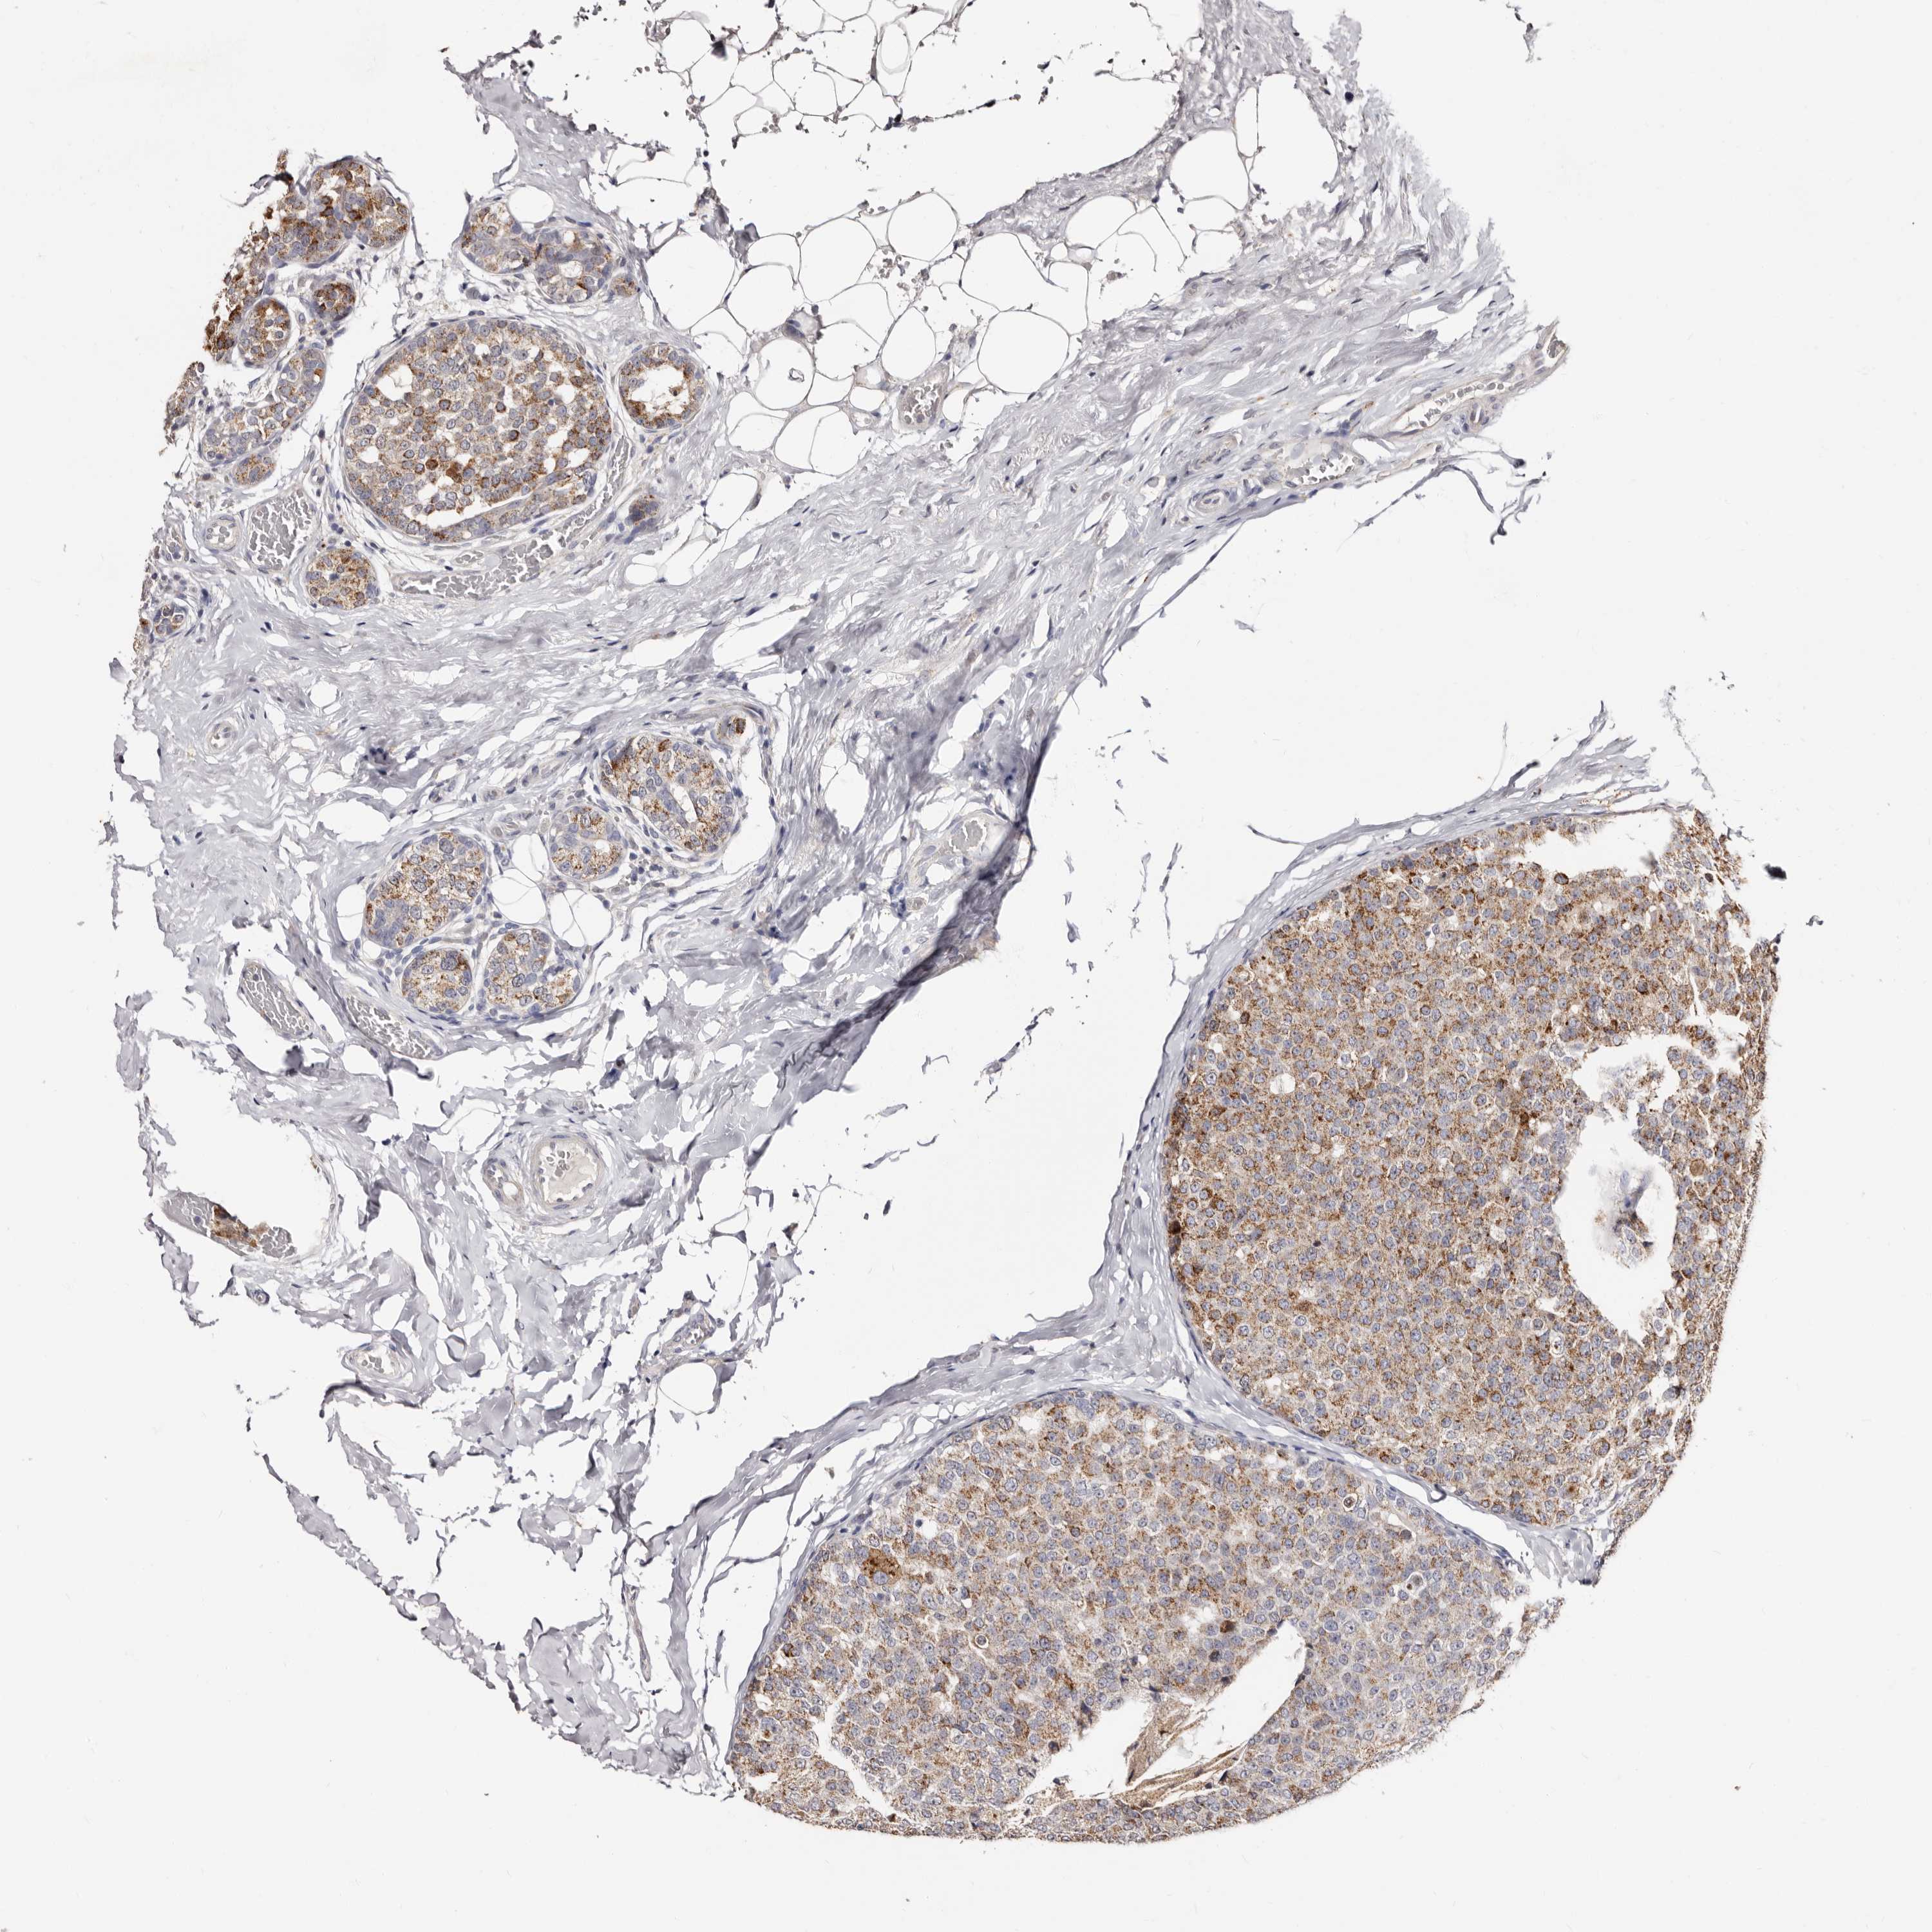

CANCER BREAST CANCER Show tissue menu

BRCA TCGA BRCA VALIDATION PROTEIN EXPRESSION